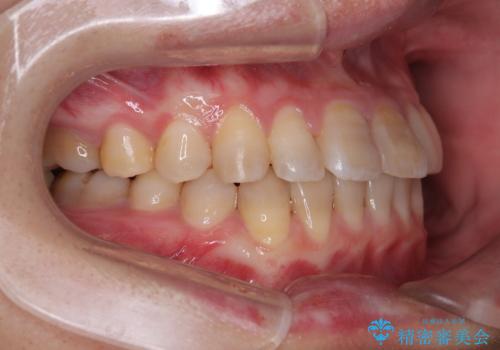

上顎が側方に拡大されて歯が並ぶスペースを確保できました。

それに伴い下顎の歯列も拡大され、舌側に倒れているのが改善されました。